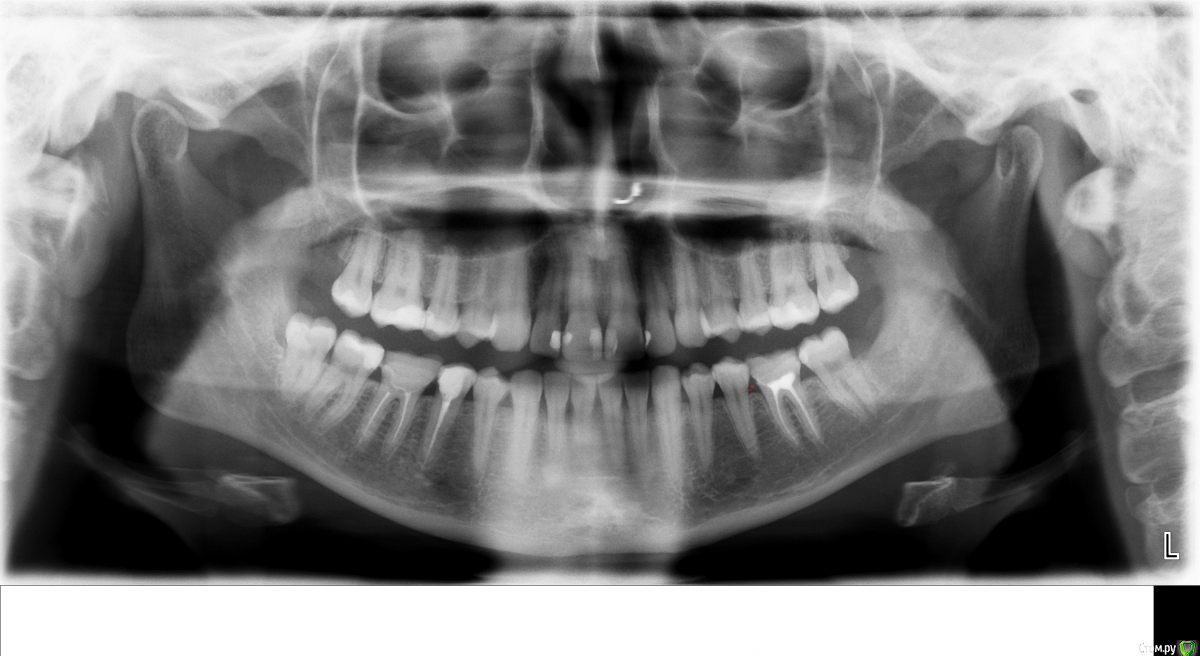

Viktoryaa Опубликовано 26 ноября, 2015 Автор Поделиться Опубликовано 26 ноября, 2015 Вот еще прикрепляю снимок 2014 года-в пазухе ничего нет.В носу на снимке это сережка Ссылка на комментарий